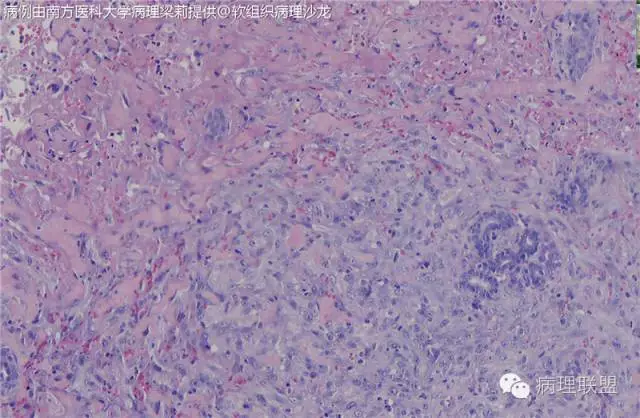

而复合性血管内皮瘤则是由良性、中间性和恶性的成份组成,也是浸润性生长,常常侵犯皮下脂肪组织,此例细胞形态由梭形细胞、卵圆形细胞及上皮样细胞组成,形态可见良性区域、中间性区域及高分化血管肉瘤或上皮样血管肉瘤区域,因此,似乎复合性血管内皮瘤更妥。此类肿瘤可以发生于婴幼儿。当然与Kaposi型血管内皮瘤一样,同属中间性血管瘤,只是后者,若肿瘤体积大,可出现Kasabach-Merritt综合征。

个人觉得应该是皮下纤维素渗出导致的内皮细胞旺炽性增生,局部呈内皮细胞乳头状增生,不认为是迷路样吻合;可能是婴幼儿血管瘤破裂诱发,也可能是血管畸形诱发。

注意活跃增生的内皮细胞总是与纤维素关系密切,并非穿插浸润的真皮胶原束。

混合型血管内皮瘤虽是混合各种形态,但是其主要成份一定是内皮瘤成份,上皮样血管内皮瘤或网状血管内皮瘤成份,其它血管肉瘤,血管瘤次要。@广医二院_病理科_梅开勇 仔细看了,好像是胶原。

这种形态若在老年人头面部就是血管肉瘤,而在婴幼儿就降级了。